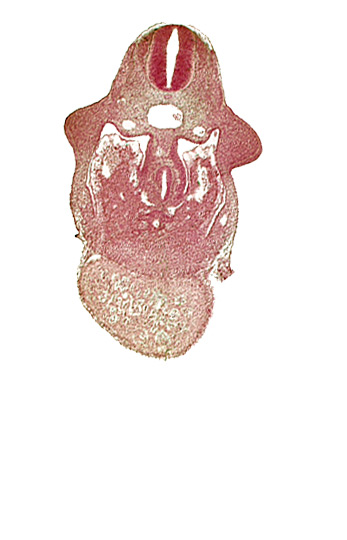

Carnegie Embryo #836 | Location: 08-03-03

Keywords: alar plate(s), basal plate, coelomic cavity, common aorta, common ventricle, dermatomyotome 9 (C-5), dorsal pancreatic bud, duodenum primordium, hepatic lamina(e), hepatic sinusoid, hepatocardiac vein, postcardinal vein, septum transversum, specialized coelomic wall, upper limb bud

Source: The Virtual Human Embryo.